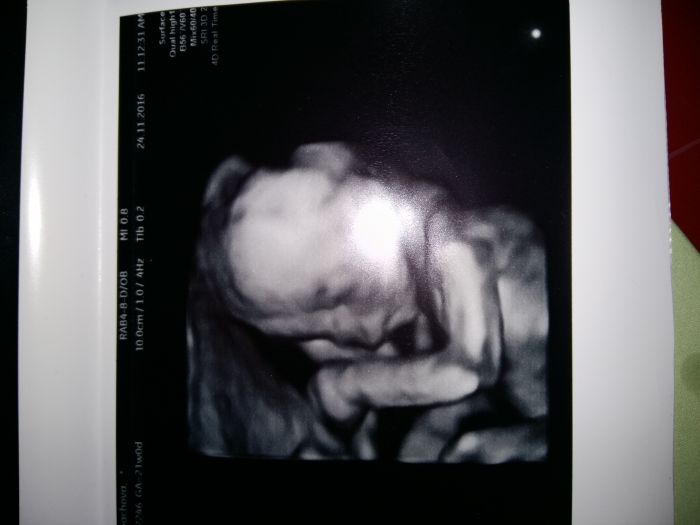

, ale sleduji vas bedlivě... Přeji všem hlavně zdravíčko a zdravá miminka... Zkusím dát fotecku malýho Lukáška

[957596] Jee to jsou krásný fotečky :)) Mně na screeningu 3D nedělala, ani mi to nenabídla. Tak jsem se na to včera ptala v poradně, a jsem objednaná na 23.12., tak snad nám Adámek ukáže před Vánoci tvářičku a budeme mít hezkej dáreček. Včera v poradně jsem se musela smát...při UTZ byl malej krásně otočenej k nám, bylo vidět jak otvírá pusinku a jakoby mlaskal. Měla jsem zrovna v puse bonbon, třeba to cítil